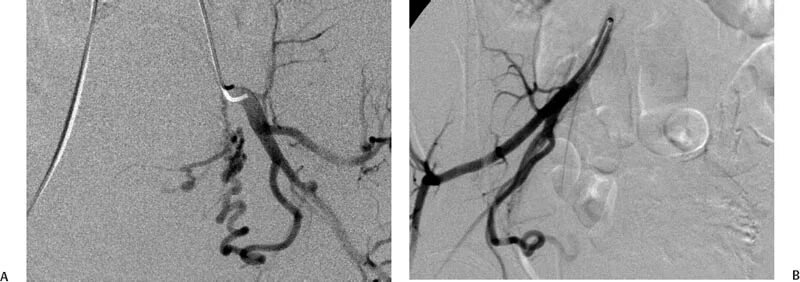

Эмболизация гемангиомы